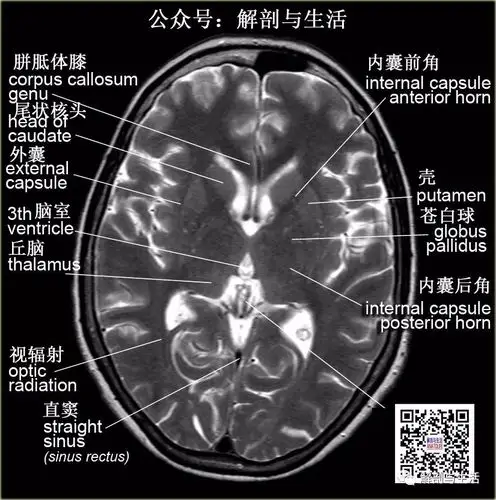

基底节区血供图

基底节区解剖与定位(二)|基底节区|基底|丘脑|位置|内囊|-健康界

基底核基底神经节